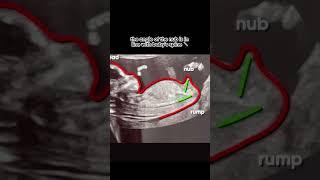

AI Gender Reveal app in the world, NubX #pregnancy #babygender #genderexpression #pregnant

Nubx: Gender Reveal, Baby Scan